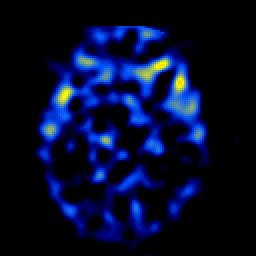

SPECT TL Study #4 -- Slice #24

[Home][Help][Clinical][Tour 1][Tour 2][Tour 3] Slice 24